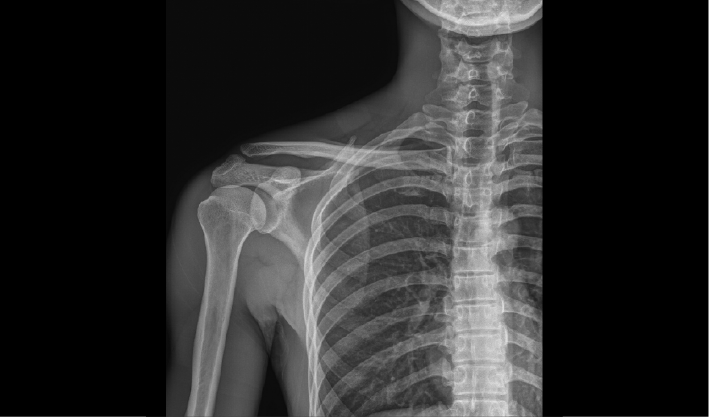

配合十軸智能全自動操控,實現六向跟蹤和一鍵自動擺位切換,融合高端配置,帶來一流的圖像,簡便操控,快捷流程,輔助醫生快速精準診斷。

消除線噪聲的同時不損失圖像細節,保持邊緣和分辨率,不會引入新偽影,增加圖像銳利度。